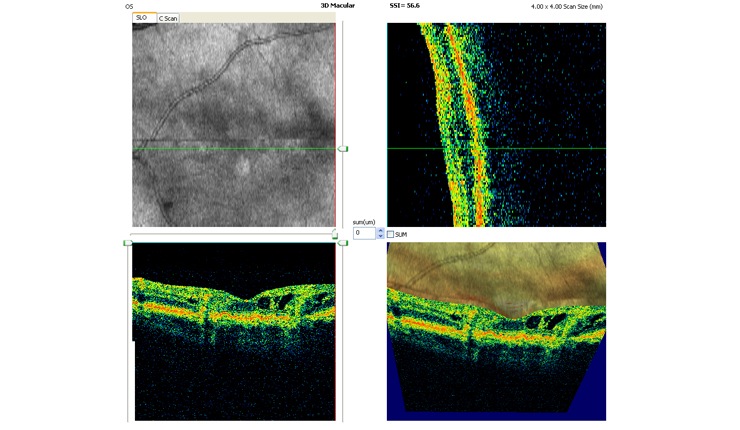

3D OCT of retinal angiomatous proliferation (RAP) showing news vessels tracking through the retina and associated intra-retinal oedema.